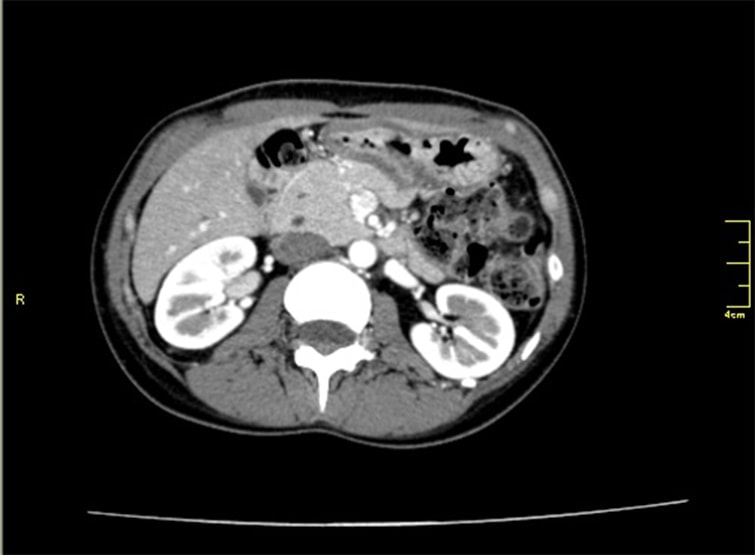

CT検査(膵臓)